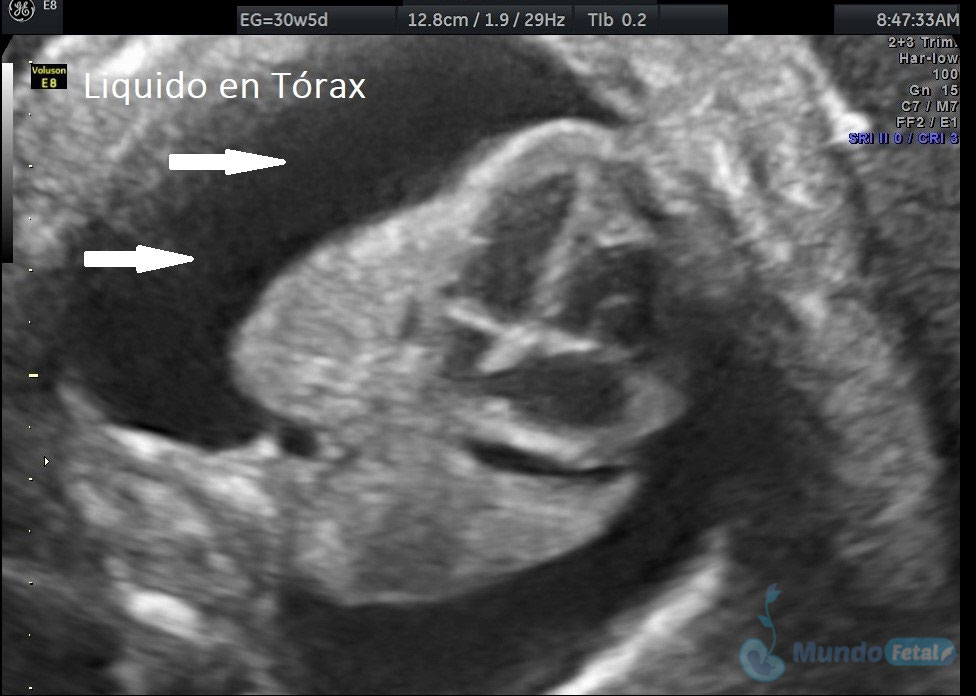

Ultrasonido Nivel II, Patología Fetal

Estudio llevado a cabo en todo bebe, en quien se haya detectado alguna alteración anatómica o marcador de riesgo, valorando todos sus órganos, aparatos y sistemas, de manera específica y detallada.